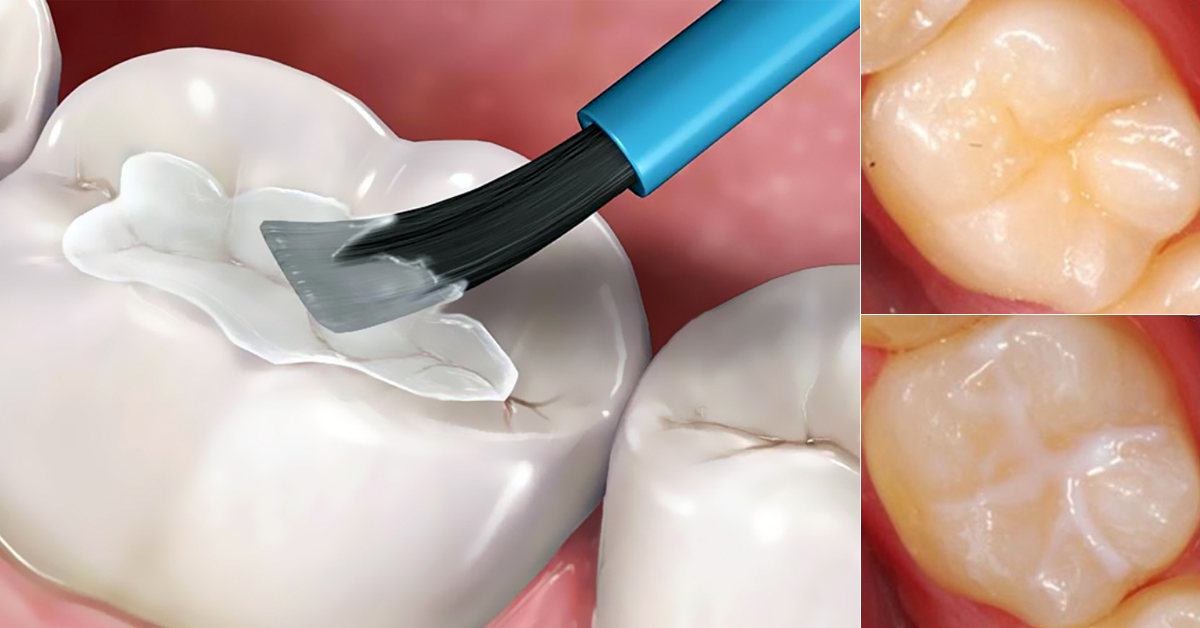

Le sigillature dentali (o “sigillanti pit & fissura”) sono un trattamento preventivo che consiste nell’applicare un sottile rivestimento protettivo su quelle superfici dei denti che sono più difficili da pulire, in particolare i solchi delle cuspidi dei molari e premolari.In particolare:

- Il materiale sigillante (resina, vetroionomerico o ibrido) viene applicato su queste superfici dopo una preparazione minima, creando una barriera che riduce l’attacco della carie.

- Pulizia della superficie: Si lava accuratamente la superficie del dente (molare/premolare) per rimuovere placca e residui;

- Preparazione dello smalto: Viene applicata una soluzione mordenzante (acido) per pochi secondi, allo scopo di favorire l’adesione del materiale sigillante;

- Protezione e isolamento: Il dente viene isolato dalla saliva (spesso con cotone o diga in gomma) per garantire che il materiale aderisca bene;

- Applicazione del sigillante: Il materiale liquido viene inserito nei solchi e ossificato o polimerizzato (ad esempio con luce a LED) fino a diventare una pellicola dura;

- Controllo dell’occlusione: Si verifica che il dente non “si alzi” troppo nella masticazione e si conferma la corretta occlusione. La sensazione alterata di morso è generalmente temporanea